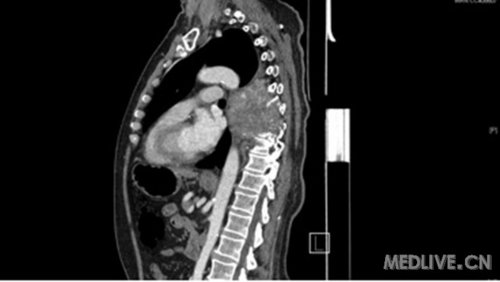

TitleBig, hypervascular paraspinal ganglioma, eroding thoracic vertebrae and ribs

大的富含血管的脊椎旁神经节瘤,侵袭胸椎和肋骨

Description: CT scan image of a huge paraspinal ganglioma extending from T4 to T9 and eroding T7 and T8 vertebrae and ribs, in close proximity to aorta and left main bronchus but not invading them.This paraganglioma was found to be hypervascular on spinal angiography.

CT扫描图像,一个巨大的脊椎旁神经节瘤,从T4到T8脊椎,侵袭了T7、T8脊椎和肋骨,非常接近主动脉和左主支气管但并未侵犯,脊髓血管造影发现这个神经节瘤富含血管。

1. Paraspinal ganglioma, axial CT scan

脊椎旁神经节瘤 CT轴位扫描